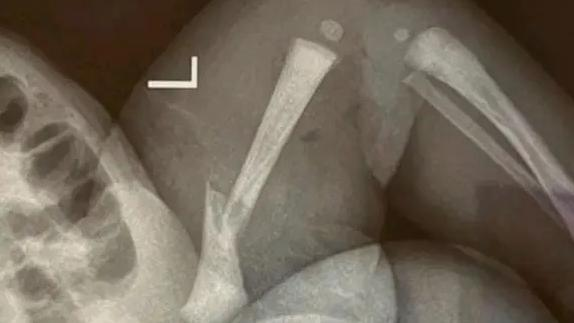

·江苏靖江新生儿骨折家长质疑系医疗事故,靖江市人民医院:手法不熟导致。